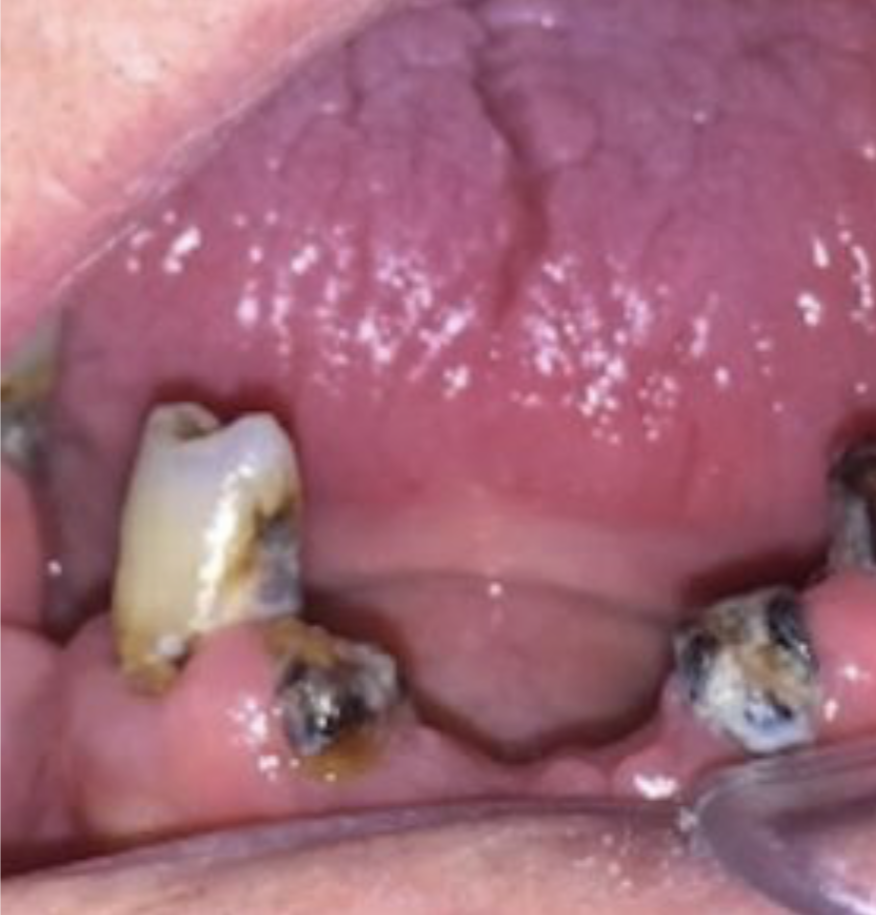

Patient outcome following ZIP-Flap reconstruction — eyes obscured for privacy

The ZIP-Flap

A technique redefining cancer rehabilitation

Fixed zygomatic implant-retained prosthesis following ZIP-Flap reconstruction

The Zygomatic Implant Perforated (ZIP) Flap combines free flap reconstruction with simultaneous intraoperative zygomatic implant placement — enabling fixed dental rehabilitation within weeks of ablative surgery for low-level maxillary malignancy.

First described in 2017 and supported by a prospective cohort of 35 consecutive cases, the ZIP Flap is rapidly becoming international standard of care. A dedicated training programme operates annually at Keele Medical School.